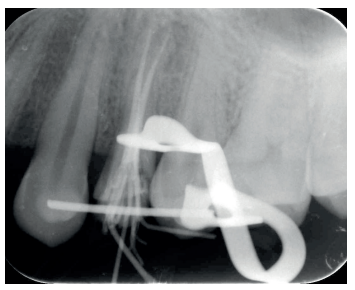

Una vez se hubo posicionado el diente 2 mm supragingival, se procedió a la ferulización con alambre de acero a los dientes adyacentes (Figuras 3 y 4) y la eliminación de cualquier tipo de oclusión, utilizando topes oclusales en los segundos molares inferiores. La ferulización se mantuvo durante dos semanas, coincidiendo con el momento de la endodoncia (Figura 5). El paciente fue citado para las revisiones periódicas y posteriormente para la rehabilitación del diente, una vez hubieron concurrido 6 semanas desde la extrusión, en las que se haya obtenido una cicatrización de los tejidos de soporte supracrestales10. En este momento, tras comprobar signos clínicos, periodontales y radiográficos saludables, se citó al paciente para el tallado y la confección mediante flujo digital (Cerec® System) de una endocorona de disilicato de litio (e.max®, Ivoclar Vivadent). El acondicionamiento de la corona se realizó con ácido fluorhídrico y silano, y para la cementación se utilizó cemento de resina (Calibra®, Dentsply Sirona).

adyacentes, tras la extrusión quirúrgica.

la extrusión, tras la endodoncia y retirada de la ferulización.